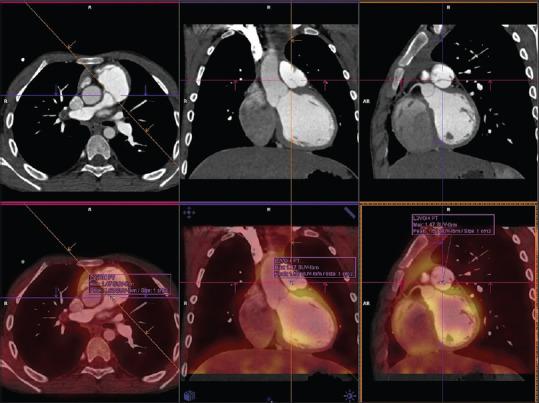

This cross-sectional study include patients operated between 2007 and 2012 (n = 92). A sample of 19 patients was selected for this study which had a follow-up of more than 3 years. This includes patients with no TAP (n = 4) and with TAP and valve substitute, a monocusp (n = 11) or a tricuspid valve (n = 4) at neopulmonary annulus. Patients underwent echocardiography for assessment of right ventricle function and 18 fluoro-deoxyglucose PET CT scan for measurements of valve substitute at neopulmonary annulus. The target to blood ratio (TBR) of uptake of glucose by monocusp was measured at the cooptation edge of the neopulmonary valve.

The median age of the patients is 14 (9 - 37). RV function is preserved (TAPSE 18.9 (10.6 - 22.8)) at a mean follow-up of 4 years (3-9). The measurements of monocusp shows a shrinkage in height of the cusp by 35.5% (70% - 1.0%) and length by 7% (-44% - +104%). There was less shrinkage observed in patients below 15 years of age. The TBR of monocusp was 0.945 (0.17 - 3.35) with a strong correlation between the TBR values of aortic valve leaflet and monocusp leaflet of same patient.